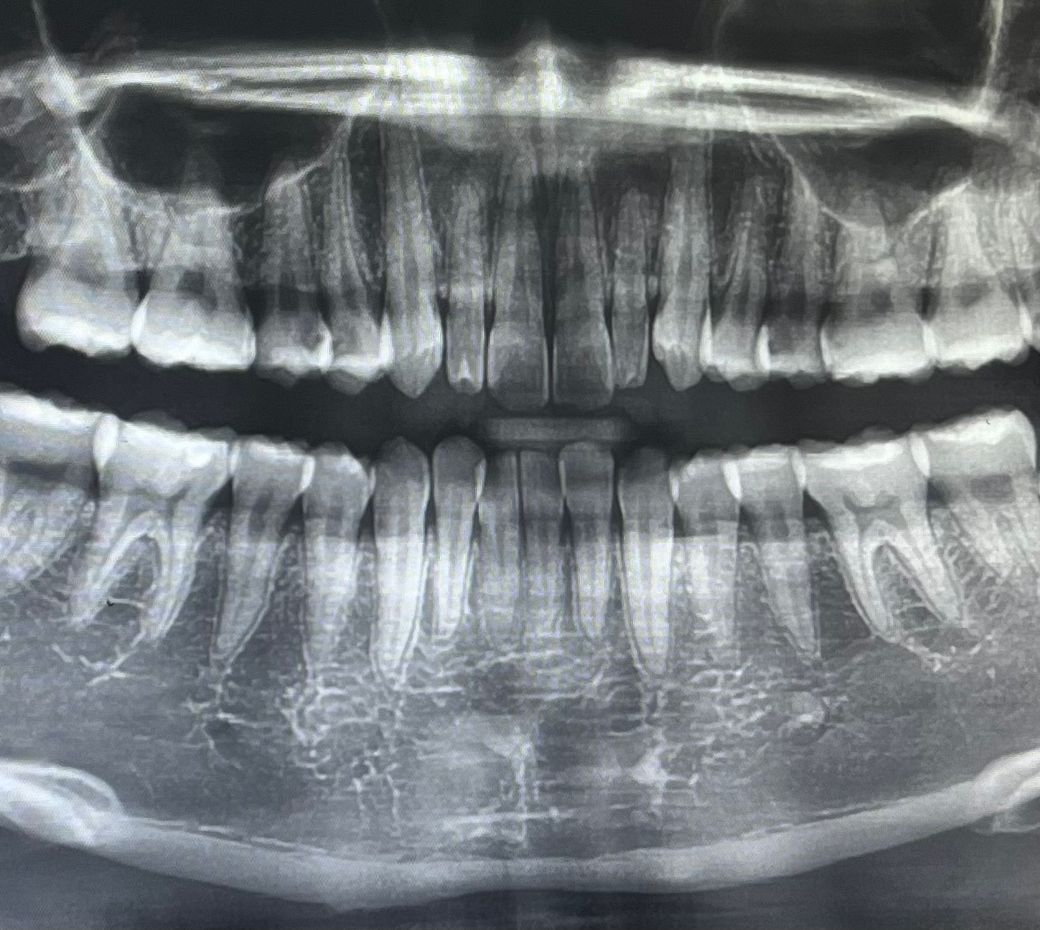

충치 엑스레이를 찍었습니다 ! 충치 치료 신경 치료를 해야할까요 ?

치과에서 엑스레이를 찍었는데 위에 이 세 개가 충치가 생겼다고 말씀해주셨어요 ! 세 개다 신경치료까지 해야할거 같다고 말씀해주셨는데 신경 치료까지 해야할까요 ?? 20대인데 신경치료 하면 신경을 죽이는 거라고 해서 걱정이에요 이가 아프지는 않고 차가운거 먹을 때 한 번씩 시린 정도입니다 크라운 치료까지 해야할까요?

1 .엑스레이상으로 보이는 충치는 꽤 깊어보입니다.

2. 신경치료 가능성이 큽니다.

3. 신경치료하면 크라운은 합니다. 세트입니다.